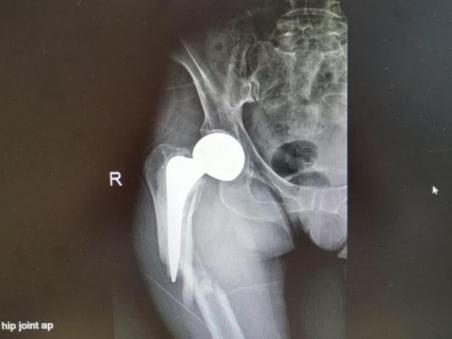

为提升区域内基层医疗机构糖尿病足诊疗服务能力、促进青年医师对糖尿病足的规范化诊治水平,遵义市第二城市医疗集团总院(贵州航天医院)圆满举办贵州省继续医学教育项目——胫骨横向骨搬移技术治疗糖尿病足专题研讨班。 贵州航天医院党委委员、副院长彭亮出席会议并致辞,遵义市第二城市医疗集团各成员单位,以及红花岗区、汇川区、绥阳县、桐梓县等多个区县的基层医疗机构骨干医师参加会议。 研讨班 本次研讨班以胫骨横向骨搬移技术在糖尿病足治疗中的应用为核心主题,围绕糖尿病药物治疗与生活方式管理策略、围手术期血糖精准调控要点、胫骨横向骨搬移技术典型病例深度解析、糖尿病足的临床分型与个体化治疗方案制定等临床实践中的热点与难点展开深入探讨,通过专题授课、案例研讨、互动交流等多元化形式,为参会者搭建了理论与实践结合的学习平台。 此次研讨班不仅为区域内基层医院搭建了学术交流与经验共享的平台,更对推动糖尿病足预防、诊断与治疗的规范化、系统化发展起到了积极作用,有效助力青年医师更新专业知识体系、提升临床技能,为进一步保障区域内糖尿病足患者的健康奠定了坚实基础。 贵州航天医院骨科专家简介 陈明勇 骨一科主任,副主任医师 临床擅长:从事创伤骨科工作约20年,对骨缺损、骨不连、骨肿瘤、肢体畸形等的肢体矫形重建及功能重建,慢性化脓性骨髓炎的根治治疗、糖尿病足的保肢治疗、快速康复理念(ERAS)下的老年骨折的诊治,四肢复杂骨折的诊治,四肢骨折等微创手术治疗具有丰富的临床经验。 2004年毕业于遵义医学院临床专业,曾在中国人民解放军总医院、广西医科大学第一附属医院、上海第六人民医院骨科进修。中国中西医结合学会骨伤科专业委员会横向骨搬移治疗糖尿病足及微血管网再生学组首届委员,遵义市医学会创伤分会常务委员。 瞿 晖 骨科党支部书记,骨二科主任,副主任医师 临床擅长:对骨科的常见病、关节外科、脊柱外科及运动医学疾病的诊治具有丰富的临床经验,熟练掌握骨科手术操作技术。 毕业于遵义医学院临床医学系,2005年前往广州中山大学第一附院骨显微医学部进修学习,2011年前往成都华西医院进修学习,并多次在省内外学习骨科相关知识,是中华医学会骨科分会会员。 赵小锋 中共党员,骨二科副主任,副主任医师 临床擅长:从事骨科临床工作11年,对骨科常见病、多发病诊疗有较为丰富的临床经验,擅长脊柱相关疾病诊断及治疗,尤其是颈、腰、腿疼痛疾病诊断及治疗,擅长胸腰椎骨折微创经皮穿刺内固定术、经皮穿刺椎体成形术、经皮穿刺脊柱内镜下腰椎间盘摘除术、单纯开创腰椎间盘摘除术、腰椎滑脱复位椎间植骨椎融合内固定术、腰椎管狭窄减压融合内固定术及人工髋、膝关节置换术等。 2012年毕业于遵义医学院外科学专业硕士研究生,2019年参加“遵义市115医学人才精英计划”于上海交通大学第一附属医院培训学习,2023年于北京大学第三人民医院脊柱外科进修学习,曾获得遵义市优秀医师荣誉称号。 遵义市手外科第一届委员,遵义市医学会创伤分会第一届委员,遵义市医学会创伤分会第二届委员,贵州省康复医学会第三届脊柱脊髓专业会委员,遵义市医学会烧伤与整形外科学分会委员,发表论文5篇,其中国家级核心期刊1篇,SCI论文1篇,主持市级课题1项并结题,参与市级课题2项。 赵兴东 骨科主任医师 临床擅长:擅长骨科的常见病及各种创伤、四肢骨折创伤修复、骨感染、手足疾病的诊治和手足体表畸形的矫形整复,熟练掌握骨科四肢骨病及创伤的手术操作技术,尤其在四肢关节复杂性损伤、手足外伤、组织缺损创面、难治创面的皮瓣修复方面及平足、高弓足矫形方面及四肢慢性疼痛诊治、康复方面具有丰富的临床经验。 硕士研究生,毕业于遵义医学院临床外科系,2015年前往山东省立医院手足外科进修学习;遵义市医学分会创伤分会第一、二届委员,遵义市手外科医学会第二委届员会常务委员;在省级及省级以上期刊发表文章9篇,参编著作2部,参与主持并完成市级课题1项,参与市级课题2项、省级课题1项。 张艳金 中共党员,骨科副主任医师 临床擅长:从事骨外科工作16年,对复合伤、多发伤的救治、四肢骨干骨折、关节周围骨折、骨肿瘤、骨髓炎等诊治具有丰富的临床经验。 中共党员,硕士研究生,2006年本科毕业于山西医科大学第二临床医学院,2011年研究生毕业于北京军区总医院;在“老年COPD患者合并髋部骨折的诊治”国际合作课题组研究两年,在老年髋部骨折的诊治方面具有丰富的经验,并发表论文6篇;主持遵义市级课题1项,承担遵义医科大学的临床教学工作,获得遵义医科大学优秀带教老师荣誉。编撰有《骨科疾病诊疗精粹》一书,开展2项新技术,编撰地方规范《务川自治县创伤骨科常见疾病诊疗规范》一书。 张俊凯 骨科副主任医师 临床擅长:从事骨科临床工作28年,对创伤骨折、骨感染、骨缺损、骨不连等外科诊治,四肢骨折的微创手术治疗,四肢复杂骨折(如关节内粉碎性骨折、多发骨折等)的损伤控制及手术治疗等具有丰富的临床经验。 1995年毕业于遵义医学院临床专业,2009年前往复旦大学附属医院骨科进修1年。 卢懿明 中共党员,骨科副主任医师 临床擅长:从事骨科工作18年,对创伤骨折、四肢骨折的微创手术治疗、四肢复杂骨折(如关节内粉碎性骨折、多发骨折等)的损伤控制及手术治疗,尤其是髋部骨折的PFNA等微创技术,踝关节骨折、膝关节周围骨折的Mipo微创技术等具有丰富的临床经验,开展了4项新技术,发明6项新型专利技术。 2005年毕业于遵义医学院临床专业,2017年,前往南方医科大学第三附属医院骨科进修半年,回院后运用Mipo技术对骨干骨折及干骺端骨折的治疗技术,同时积极开展骨盆骨折、髋臼骨折腹直肌外侧切口的应用;发表了多篇专业论文,经常参与省内外学术交流会授课,获得医院荣誉称号多个。 邬夏荣 骨科副主任医师 临床擅长:从事骨科工作16年,对四肢复杂骨折、骨肿瘤的诊治,尤其是足踝创伤、慢性踝关节损伤、平足症等诊疗具有丰富的临床经验。 2006年毕业于遵义医科大学临床医学专业,曾在陆军军医大学西南医院进修学习,发表多篇骨科学术论文。 余德怀 中共党员,骨科副主任医师 临床擅长:从事骨科工作10余年,对运动医学、骨关节、脊柱外科常见病、多发病的诊治具有丰富的临床经验。 硕士研究生,2011年毕业于遵义医学院临床医学专业,曾前往遵义医科大学附属医院运动医学专业进修学习;是贵州省医学会运动医学分会青年委员,西部关节镜联盟委员;发表多篇骨科学术论文。 冯 乾 骨科副主任医师 临床擅长:从事骨科工作近20年,熟练掌握骨科多发病及常见病的诊治,尤其对脊柱退变性疾病的诊断及治疗具有丰富的临床经验,主要研究脊柱微创相关治疗方式,能熟练开展椎间孔镜及UBE。 曾前往北京大学第三医院进修学习疼痛及椎间孔镜、首都医科大学友谊医院专业进修脊柱内镜;是贵州省康复医学会第三届脊柱脊髓专业委员会委员;发明专利3项、发表脊柱外科专业论文多篇。 贵州航天医院骨科简介 基本情况 贵州航天医院(原3417医院)骨科组建于1968年,前身是以创伤和断肢(断指)再植闻名于世的上海市第六人民医院骨科,中国断肢(断指)再植的奠基者、中科院院士陈仲伟等专家莅临科室指导医疗和教学,并在70年代开展了贵州省首例断肢(断指)再植手术。组建50余年来,诊治患者已逾百万,挽救了无数的伤病员,成为了保障遵义地区人民群众健康的重要支撑。 经过几代人的不懈努力,今天的骨科,已由创伤骨科发展至骨病、骨肿瘤、骨结核等领域,现有脊柱外科、关节外科、四肢创伤、手足外科四个亚专科,成为了集医疗、教学、科研于一体的综合学科,是贵州省临床重点专科、遵义市临床重点专科、遵义市骨科临床医学中心、遵义市基层骨科专科联盟理事长单位。 科室目前开放床位110张,共有医护人员50余人,副高级以上专家18人,硕士研究生15人。拥有一流骨科医疗设备多台,每年不定期选派优秀技术骨干到全国各大知名医学院校进修、学习、参观、交流,并邀请国内、国外知名专家教授来院进行交流、指导,通过不断引进国内外先进的诊疗技术,科室医疗技术水平稳步提升,为广大人民群众提供了优质的医疗服务。 专科特色 骨一科 (一)骨缺损、骨不连的肢体与功能重建 胫骨横向骨搬移技术治疗糖尿病足: (二)慢性骨髓炎的根治治疗 (三)肢体缺血性疾病如糖尿病足、脉管炎的保肢治疗 (四)皮瓣修复 (五)复杂创伤的治疗 (六)老年髋部骨折及小儿骨折快速手术 老年髋部骨折: 骨二科 (一)胸腰椎骨折微创经皮椎弓根螺钉固定术 (二)老年性骨质疏松性患者腰椎滑脱脊柱内固定术(骨水泥螺钉) (三)V形双通道脊柱内镜技术(VBE)腰椎融合术治疗腰椎退行性疾病 (四)老年性骨质疏松性骨折(PVP/PKP)术 (五)人工髋关节置换术 (六)双侧股骨头坏死人工全髋关节置换 (七)右侧全髋置换术后假体周围骨折翻修 (八)人工膝关节置换术 (九)人工膝关节假体松动翻修 (十)关节镜技术 传统手术切口 关节镜技术切口 诊疗范围 骨一科 1.四肢创伤、矫形。 2.手、足踝外科。 骨二科 End